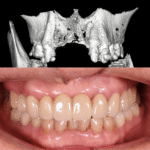

ถ้าต้องปลูกกระดูกจะมีค่าใช้จ่ายเพิ่มแล้วแต่ปริมาณวัสดุที่ใช้ประมาณ 10,000-20,000 บาทต่อซี่ ทางคลินิกจะทำการปลูกกระดูกเมื่อมีความจำเป็นเท่านั้นและทำเพื่อผลสำเร็จของรากฟันเทียมในระยะยาว โดยมีการตรวจอย่างละเอียดด้วย CT scan 3 มิติ และแจ้งค่าใช้จ่ายอย่างชัดเจนทุกครั้ง

เราเข้าใจว่าคนไข้แต่ละท่านมีความต้องการและงบประมาณต่างกัน จึงมีรากฟันเทียมหลายระดับให้คุณเลือก

คุณหมอของเราจะช่วยแนะนำ รากฟันเทียมที่เหมาะกับโครงสร้างกระดูก เหงือก การสบฟัน และงบประมาณของคุณได้อย่างเหมาะสม